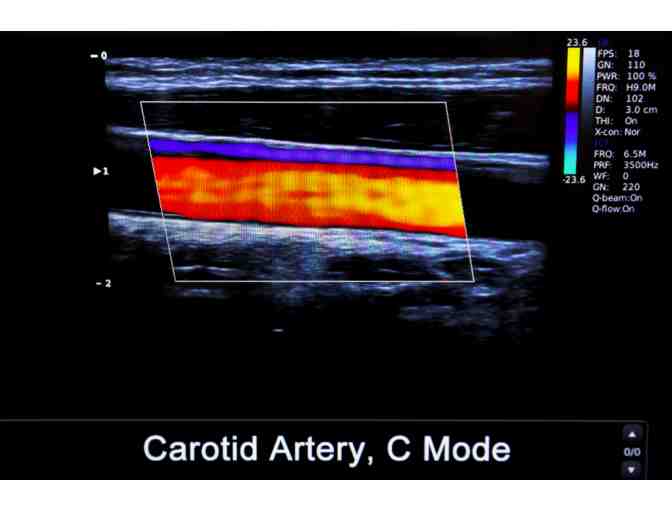

Heart disease is the leading cause of death for men and women in the United States. Stroke is the 5th leading cause of death. Preventive health screenings, which are also non-invasive, can identify risk factors that can lead to cardiovascular disease and stroke. This allows people to understand their risk of developing a condition before symptoms are present so that they can take action. As part of this screening, the individual will receive a limited EKG and a carotid ultrasound to assess plaque buildup.